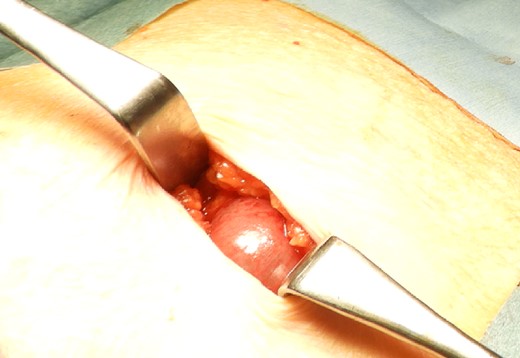

The drain was removed on postoperative day 2. On the night of the third postoperative day, the patient vomited. On the morning of the fourth postoperative day, mild abdominal pain and a ping-pong ball-sized bulge and induration were found near the surgical scar of the 5 mm port where the drain had been placed. CT confirmed an incarcerated small intestine and ileus in the 5 mm port scar where the drain had been placed (Fig. 2). Ileus removal was performed on the same day. First, the dilated wound for nephrectomy was opened, and the inside of the abdominal cavity was observed. A hanging small intestine was observed just below the 5 mm port (Fig. 3). Since it could not be conquered manually, a 2 cm vertical incision was made on the 5 mm port wound. The small intestine penetrated the anterior layer of the rectus abdominis muscle, so the fascia was carefully incised to avoid damaging the small intestine. The small intestine was returned to the abdominal cavity. The small intestine was slightly discolored (Fig. 4), but after discussion with the gastrointestinal surgeon, it was determined that it was not necrotic. No small intestine resection was performed. The wound was carefully closed using fascial sutures to prevent recurrence. The fascia was weak, likely because this patient was taking steroids. The ileus has not recurred since then. The pathological results indicated a maximum diameter of 30 mm, consistent with papillary renal cell carcinoma, classified as pT1a G3 > G2, with negative margins.